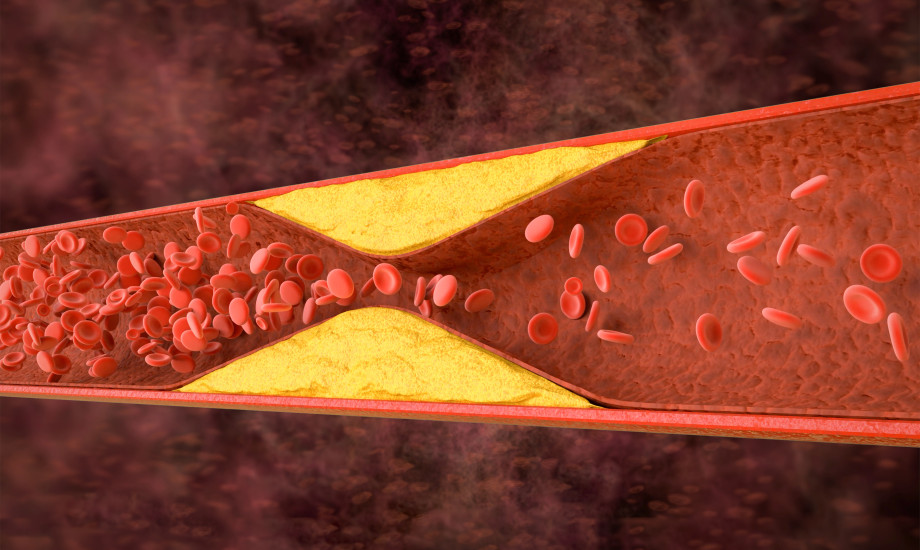

Mit dem PREVENT-Rechner kann das 10- und 30-Jahres-Risiko für ein kardiovaskuläres Ereignis abgeschätzt werden. Einer neuen Studie zufolge schließt ein niedriger PREVENT-Score eine subklinische Atherosklerose jedoch nicht aus. Hier braucht es den CAC-Score für eine Prognose zu zukünftigen kardiovaskulären Ereignissen.

© phonlamaiphoto/stock.adobe.com

© phonlamaiphoto/stock.adobe.com